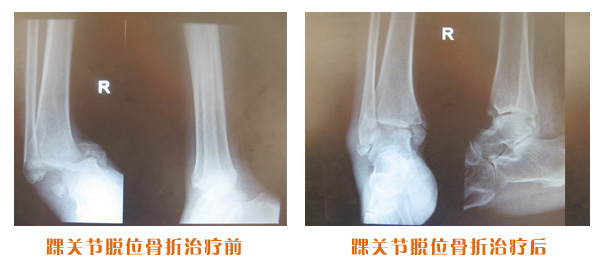

肥城市安駕莊梁氏骨科醫院是一所以梁氏手法正骨配合膏藥為特色的現代化專科醫院。

梁氏骨科術始創于清雍正年間,歷經八代,至今已有三百年歷史。據1929年泰安縣志載“梁瑞圖先生,字增生,號蓮峰,安駕莊人,精岐黃并發明接骨,凡跌打車凡跌打車軋皮不破而碎骨者......【詳細】 |